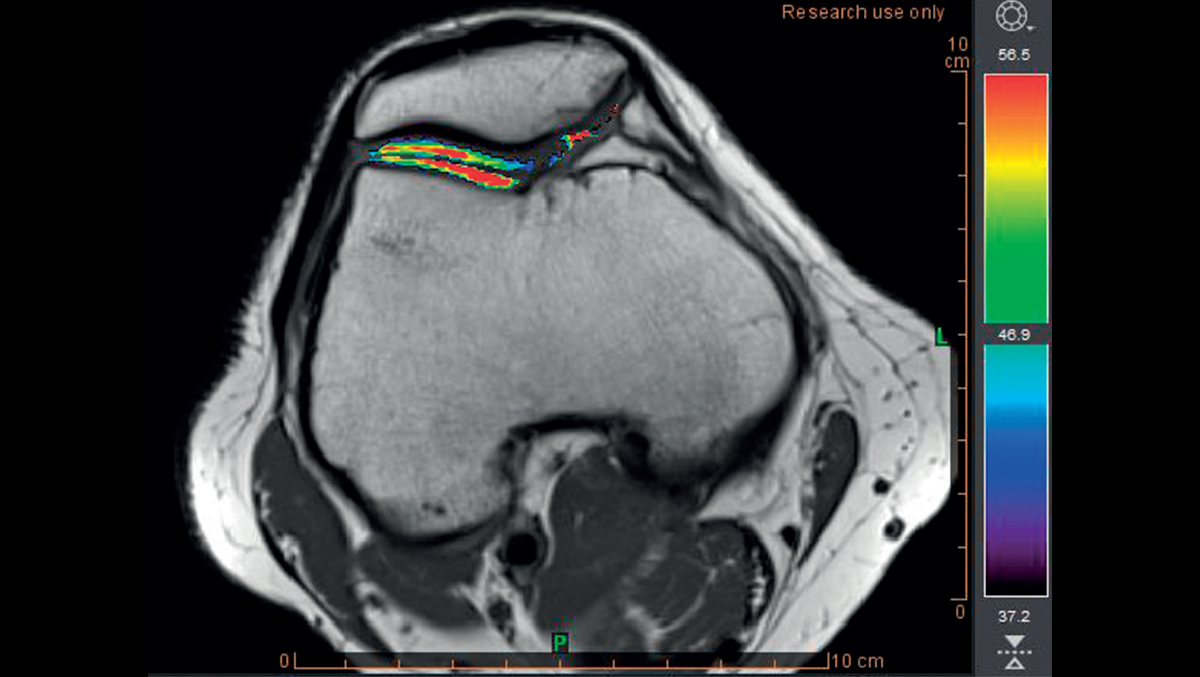

Опорно-двигательный аппарат

Диагностика и наблюдение за спортивными и ортопедическими заболеваниями

• Расчет отображения T2

• Раннее обнаружение разрушения хряща с помощью карты Thresholds T2

Опорно-двигательный

Обнаружение хрящевой ткани в группе риска с использованием пороговых значений времени релаксации T2